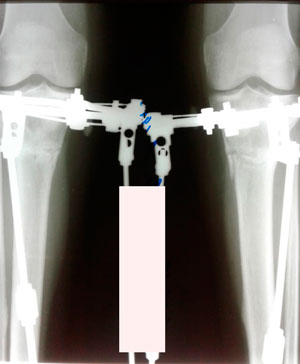

Исходник -34 года.Бишкек.

Дата операции - 26.02.2019г.

Дата снятия аппаратов - 05.06.2019г.

Срок сращения - 98 дней.